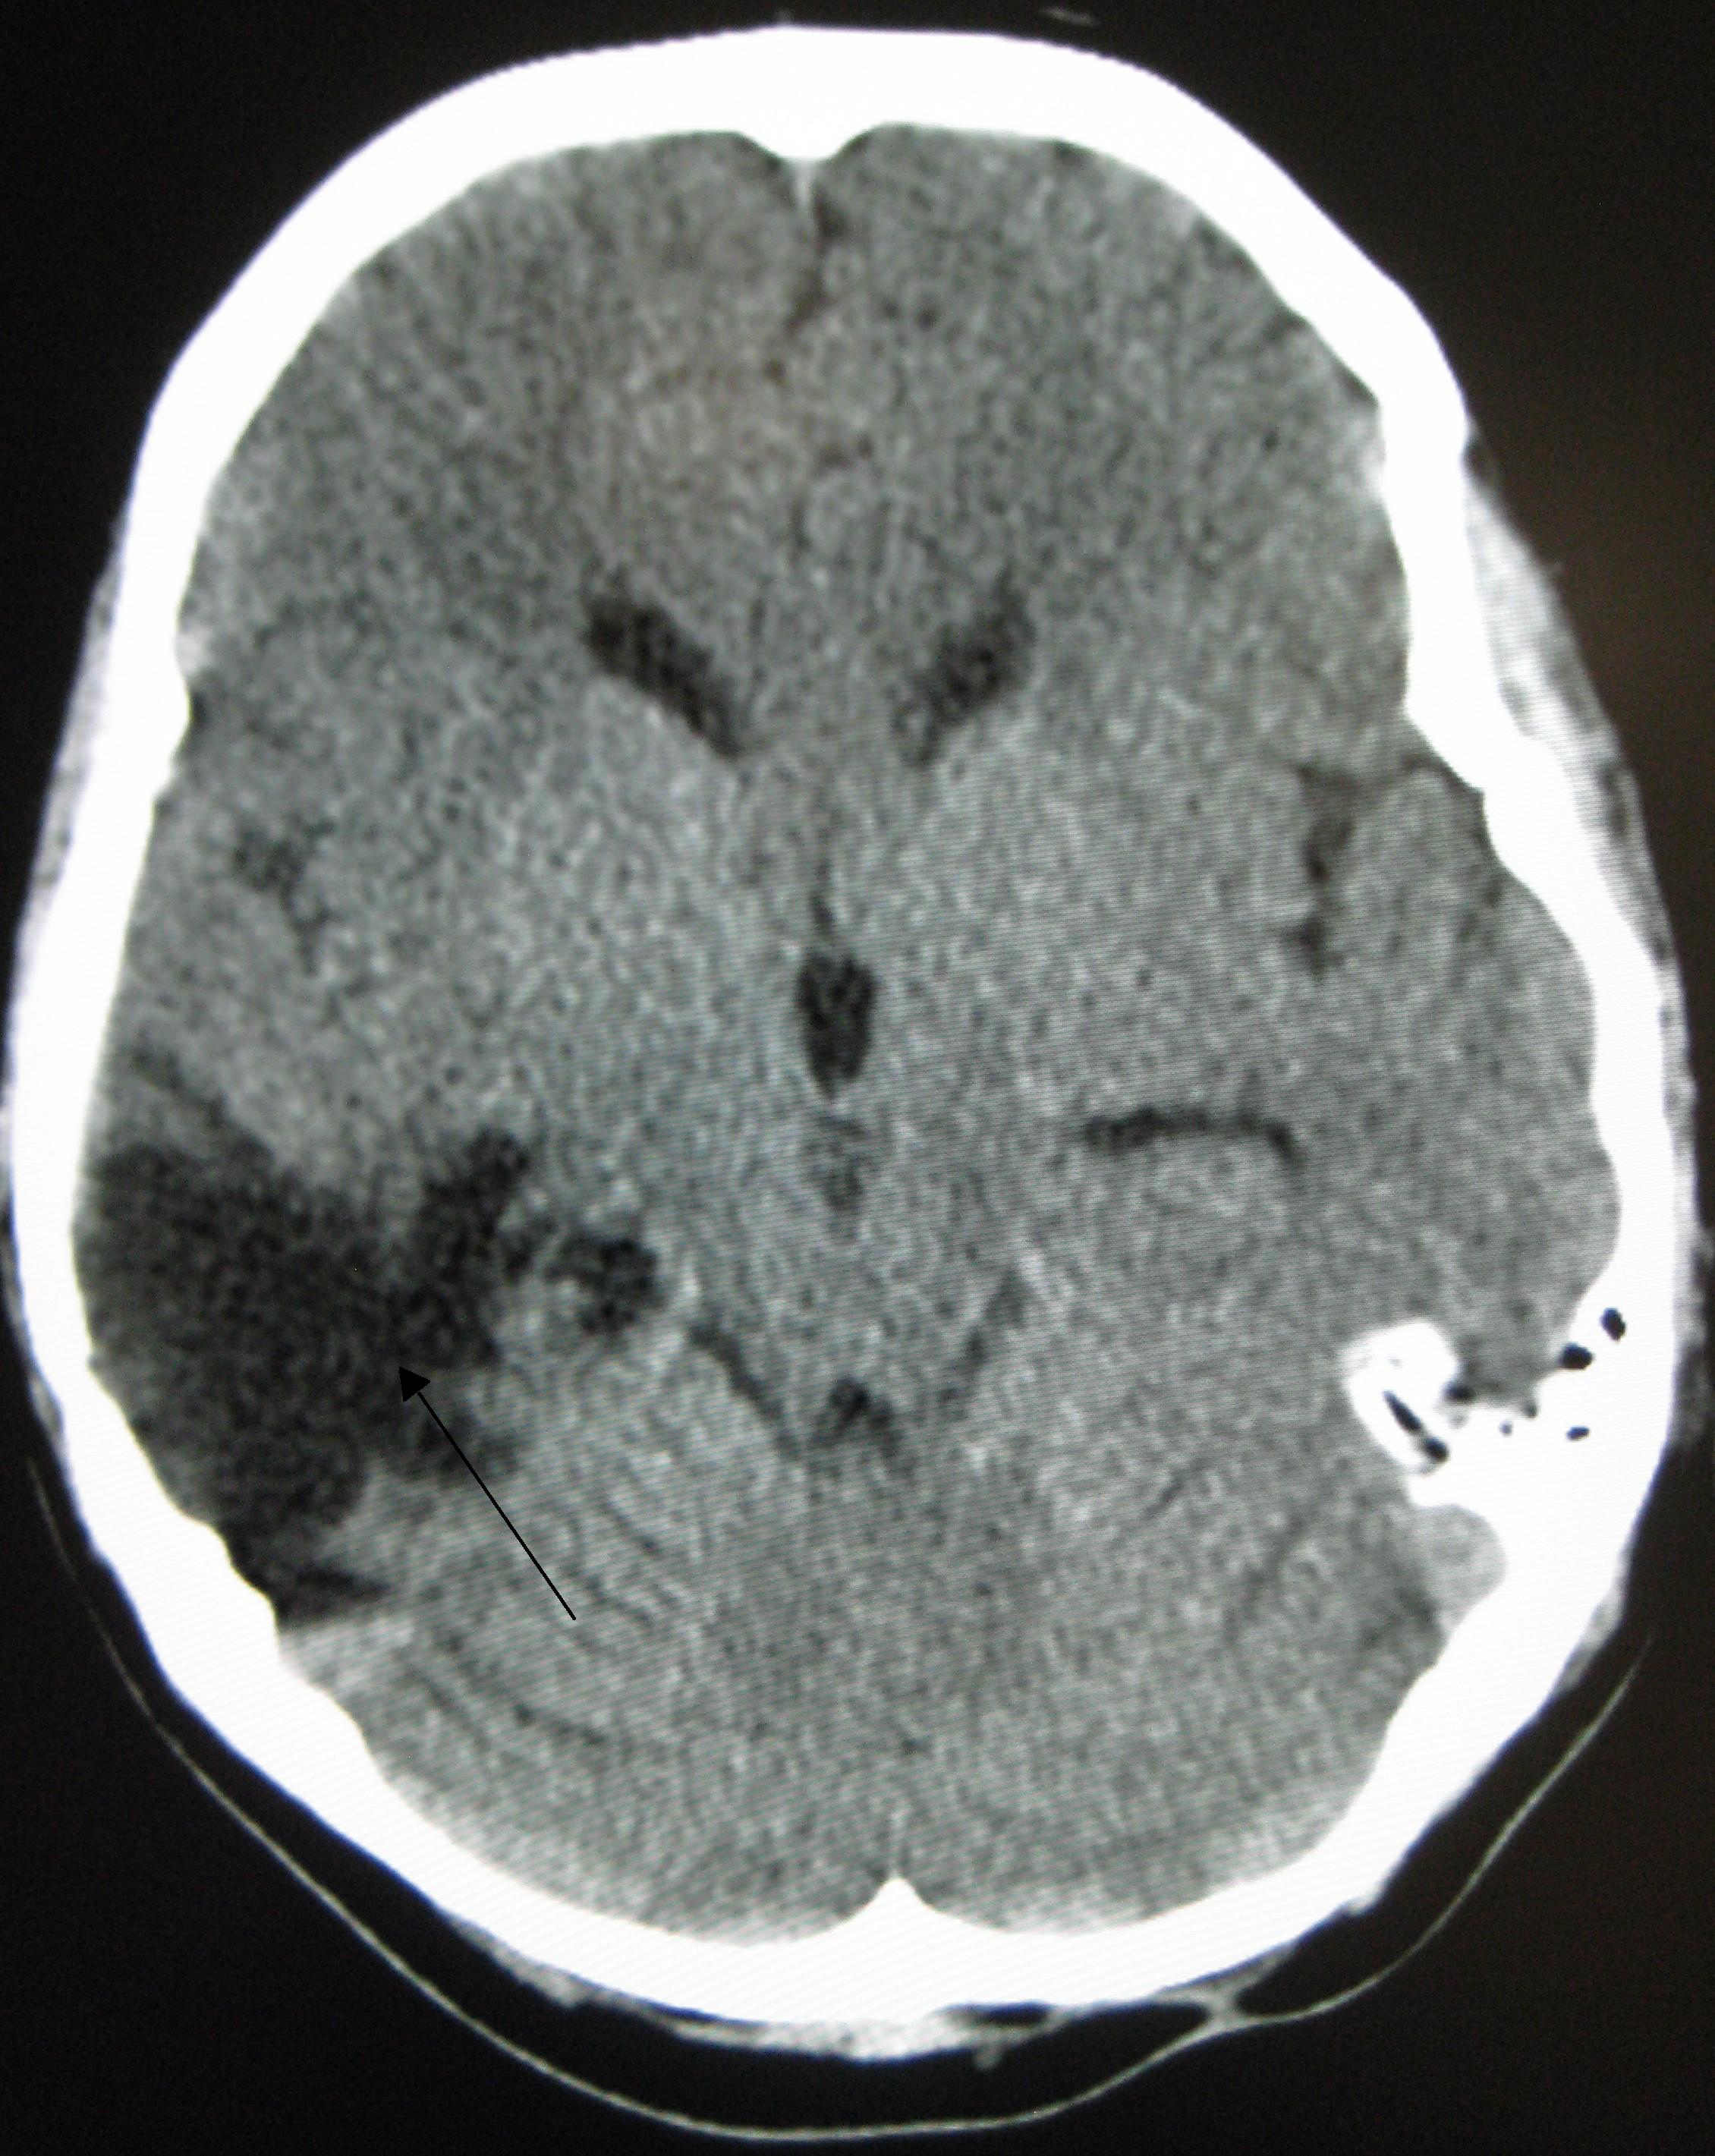

국소 손상의 한 종류인 뇌좌상은 뇌 조직이 찢어지거나 절단될 때 발생한다.[173] 특히 눈 위의 두개골 안쪽 뼈 돌출부 때문에 전전두엽 피질에서 흔하게 발생한다.[24] 뇌좌창은 뇌 조직에 멍이 드는 것으로, 혈액이 조직과 섞이는 상태를 말한다.[162] 반면 두개내 출혈은 혈액이 뇌 조직과 섞이지 않고 고이는 출혈을 의미한다.[173]

혈종 역시 국소 병변으로, 출혈로 인해 뇌 안이나 주변에 피가 고이는 것을 말한다.[7] 뇌 조직 자체에 출혈이 생기는 뇌내 출혈은 뇌막내성 병변이다. 뇌막외성 병변에는 다음과 같은 종류가 있다.[30]

- 경막외혈종: 두개골과 경막(뇌를 감싸는 가장 바깥쪽 뇌막) 사이에 피가 고이는 것.[7]

- 경막하혈종: 경막과 거미막 사이에 피가 고이는 것.[162]

- 지주막하 출혈: 거미막과 연막 사이에 피가 고이는 것.[162]

- 뇌실내 출혈: 뇌실계 안에 피가 고이는 것.[30]

외상성 뇌손상(TBI)의 진단은 병변의 상황과 임상 증거, 특히 신경학적 검사 결과를 바탕으로 의심된다.[162] 신경 영상 검사는 진단 및 예후를 결정하고 적절한 치료법을 결정하는 데 중요한 보조 수단으로 활용된다.[165] 또한, DSM-5는 외상성 뇌손상과 관련된 정신과적 후유증을 진단하는 데 사용될 수 있다.[69][70][71]

신경 영상 검사는 외상성 뇌손상의 진단 및 예후를 결정하고 적절한 치료법을 결정하는 데 도움이 된다.[165]

응급 상황에서는 컴퓨터 단층촬영(CT)이 가장 선호되는 방사선 검사다. 신속하고 정확하며 널리 사용 가능하기 때문이다.[73] 손상이 진행되었는지 확인하기 위해 추후 CT 촬영을 실시할 수도 있다.[193]